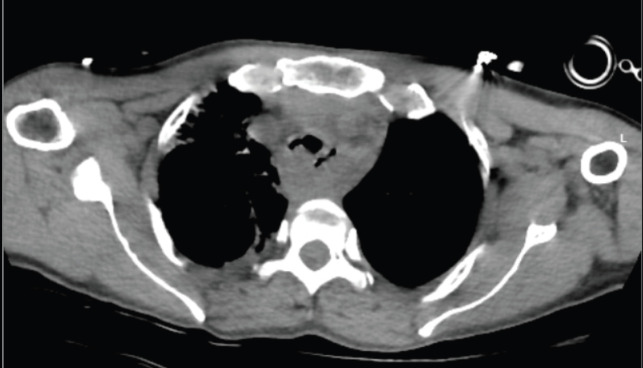

Abstract Image